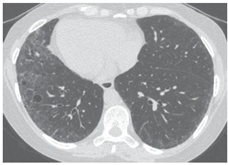

As imagens abaixo estão relacionadas a outras doenças pulmonares císticas.